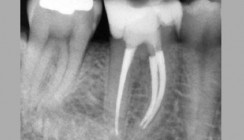

- Röntgeneinzelbild: apikale Aufhellungen mesial und distal sowie ausgedehnte interradikuläre Aufhellung, insuffiziente Wurzelkanalfüllung distal, ungefüllte Wurzelkanäle mesial, deutlich kürzere Wurzeln im Vergleich zu den Nachbarzähnen (Abb. 1)

Abb. 1: Diese Therapieoption kann Zähne retten, die bereits erfolglos chirurgisch behandelt worden sind und als extraktionswürdig gelten, da durch die Revision die eigentliche Entzündungsursache – die mikrobielle Kontamination des Wurzelkanalsystems – angegangen wird. – Abb. 2: Leider war es nicht gelungen, wie gewünscht einen ausreichend mesioexzentrischenStrahlengang zu erzielen. Da die Silberstifte gerade noch getrennt beurteilbar waren, wurde jedochauf eine erneute Röntgenmessaufnahme verzichtet. Der Kofferdam war zur Erleichterungwährend des Röntgens entfernt und die Zugangskavität speicheldicht verschlossen worden. – Abb. 3: Röntgenkontrollaufnahme nach Füllung der vier Wurzelkanäle und adhäsivemVerschluss mit Komposit. Durch die schräg resezierten Wurzeln erscheinen die Wurzelkanalfüllungen meist zu kurz. – Abb. 4: Röntgenkontrollaufnahme nach etwa zwei Jahren mit stärker exzentrischem Strahlengang (im Vgl. zu Abb. 2 und 3). Hier ist eine bessere Beurteilung der beiden mesialen Wurzelkanalfüllungen möglich. Da der Abstand der distalen Kanäle sehr klein war, ist deren separate Beurteilung weiterhin schwer. Der periapikale und interradikuläre Bereich scheint knöchern ausgeheilt zu sein; ein kontinuierlicher Parodontalspalt ist erkennbar.

Die Hauptursache für die vermutlich bereits seit Langem bestehende chronische apikale Parodontitis ist in den unzureichend aufbereiteten und gefüllten Wurzelkanälen zu suchen; zudem schien der distobukkale Wurzelkanal bei der ursprünglichen Behandlung gar nicht instrumentiert worden zu sein. Nicht selten können solche chronisch entzündlichen Zustände teilweise über Jahre hinweg von den Patienten unbemerkt bleiben und auch bei Kaubelastung keine größeren Beschwerden verursachen. Dennoch kommt es früher oder später meist zu akuten Exazerbationen – so auch in diesem Fall. Bei der Patientin konnte während der Erstuntersuchung am Zahn 46 eine lokal begrenzte Schwellung vor allem im Bereich der vestibulären Gingiva sowie ein Fistelmaul etwa 5 mm apikal des Gingivarandes beobachtet werden. Bei der vorsichtigen Sondierung des Fistelganges mit einem Guttaperchapoint mittlerer Größe kam es zu einer spontanen Pusentleerung. Der Fistelgang verlief eindeutig in Richtung des Zahnes 46, sodass bei der folgenden präoperativen Röntgenaufnahme auf den üblicherweise eingeführten Guttaperchapoint verzichtet werden konnte. Das Röntgenbild zeigte am Zahn 46 eine verhältnismäßig ausgedehnte Aufhellung, die die beiden Wurzelspitzen und den interradikulären Bereich umfasste. Zugleich waren die deutlich (vermutlich um 6 bis 8 mm) verkürzten Wurzeln auffällig (Abb. 1). Die Patientin hatte bei der Anamnese eine WSR angeführt, die an diesem Zahn vor einigen Jahren aufgrund persistierender Schmerzen vorgenommen worden war. Es ist schwer einzuschätzen, ob zusätzlich Resorptionsprozesse für die nunmehr stark verkürzten Wurzeln mitverantwortlich sind. Nachvollziehbar ist, dass eine WSR aufgrund der insuffizienten orthograden Behandlung nicht zum Erfolg führen konnte. Die mittlere Erfolgsquote eines rein chirurgischen Vorgehens beträgt lediglich 58,9 Prozent; bei vorherig er orthograder Revision steigt der Wert auf 79,6 Prozent.5 Ein Grund für die damalige Entscheidung war sicherlich die Schonung der kurz zuvor eingegliederten Keramikkrone. Dennoch hätte zunächst eine orthograde Revision durchgeführt werden müssen (und eine WSR unterbleiben sollen), da nur auf diesem Wege die in den Kanälen vorhandenen Mikroorganismen und deren Toxine entfernbar sind. Die Reinigung, Aufbereitung und Füllung eines kompletten Wurzelkanals ist über einen chirurgischen Eingriff von retrograd in der Regel nicht möglich. Bei der nun notwendig gewordenen Revision musste mit großer Sorgfalt vorgegangen werden, da nach der WSR keine physiologischen Foramina mehr vorhanden waren. Somit bestand ein erhöhtes Risiko der Extrusion von altem, infizierten Wurzelkanalfüllmaterial und Debris sowie des Überpressens von Spülflüssigkeit, wodurch das periapikale Gewebe zusätzlich geschädigt werden kann.6, 7